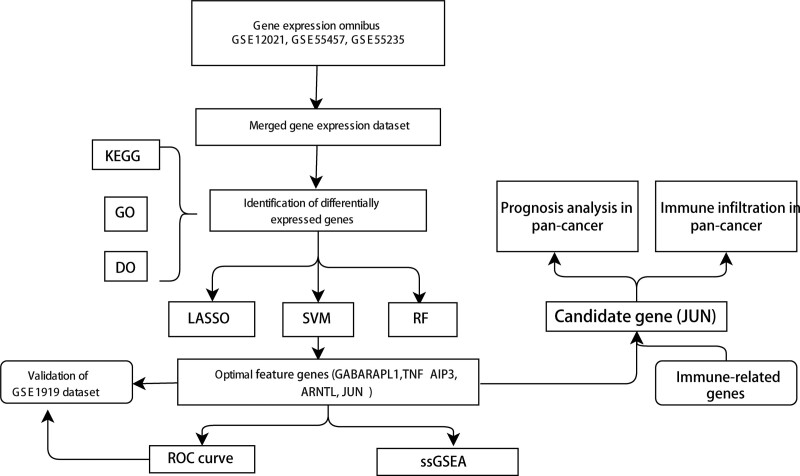

2.1. Overview of research procedures

In the present study, OA-related gene chip datasets were accessed from Gene expression omnibus (GEO-https://www.ncbi.nlm.nih.gov/geo/) open resources. Genes expressing differentially between OA tissues and normal tissue samples were identified in data from GEO database. Three popular machine learning algorithms, LASSO, SVM-RFE, and RF classifier were employed to identify the most critical feature genes for further study. Furthermore, correlation analysis of selected feature genes and the abundance of immune cells was performed.

A total of 259 FRGs were identified. The entire analysis process of this study was presented in the Figure 1. At first, we compared the genes expression levels of normal control and OA disease group to identify DEGs. When comparing the synovial tissues of 30 OA patients and 29 normal controls, we found that 126 genes were highly expressed in OA samples while 156 genes were down-regulated. The results of DEGs were shown in the volcano plot and heatmap (Figs. 2A and 2B).